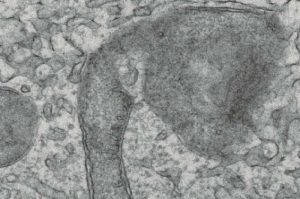

Immagine: l‘immagine a sinistra mostra cellule normali con mitocondri tubulari (rosso) e DNA (verde) nel nucleo e all’interno dei mitocondri. A destra, MxB è stato rimosso con mezzi genetici e lascia i mitocondri frammentati (rosso) con il suo genoma spostato nel citoplasma. Credito di immagine: Mayo Clinic. Il coronavirus COVID 19 sta causando il caos […]